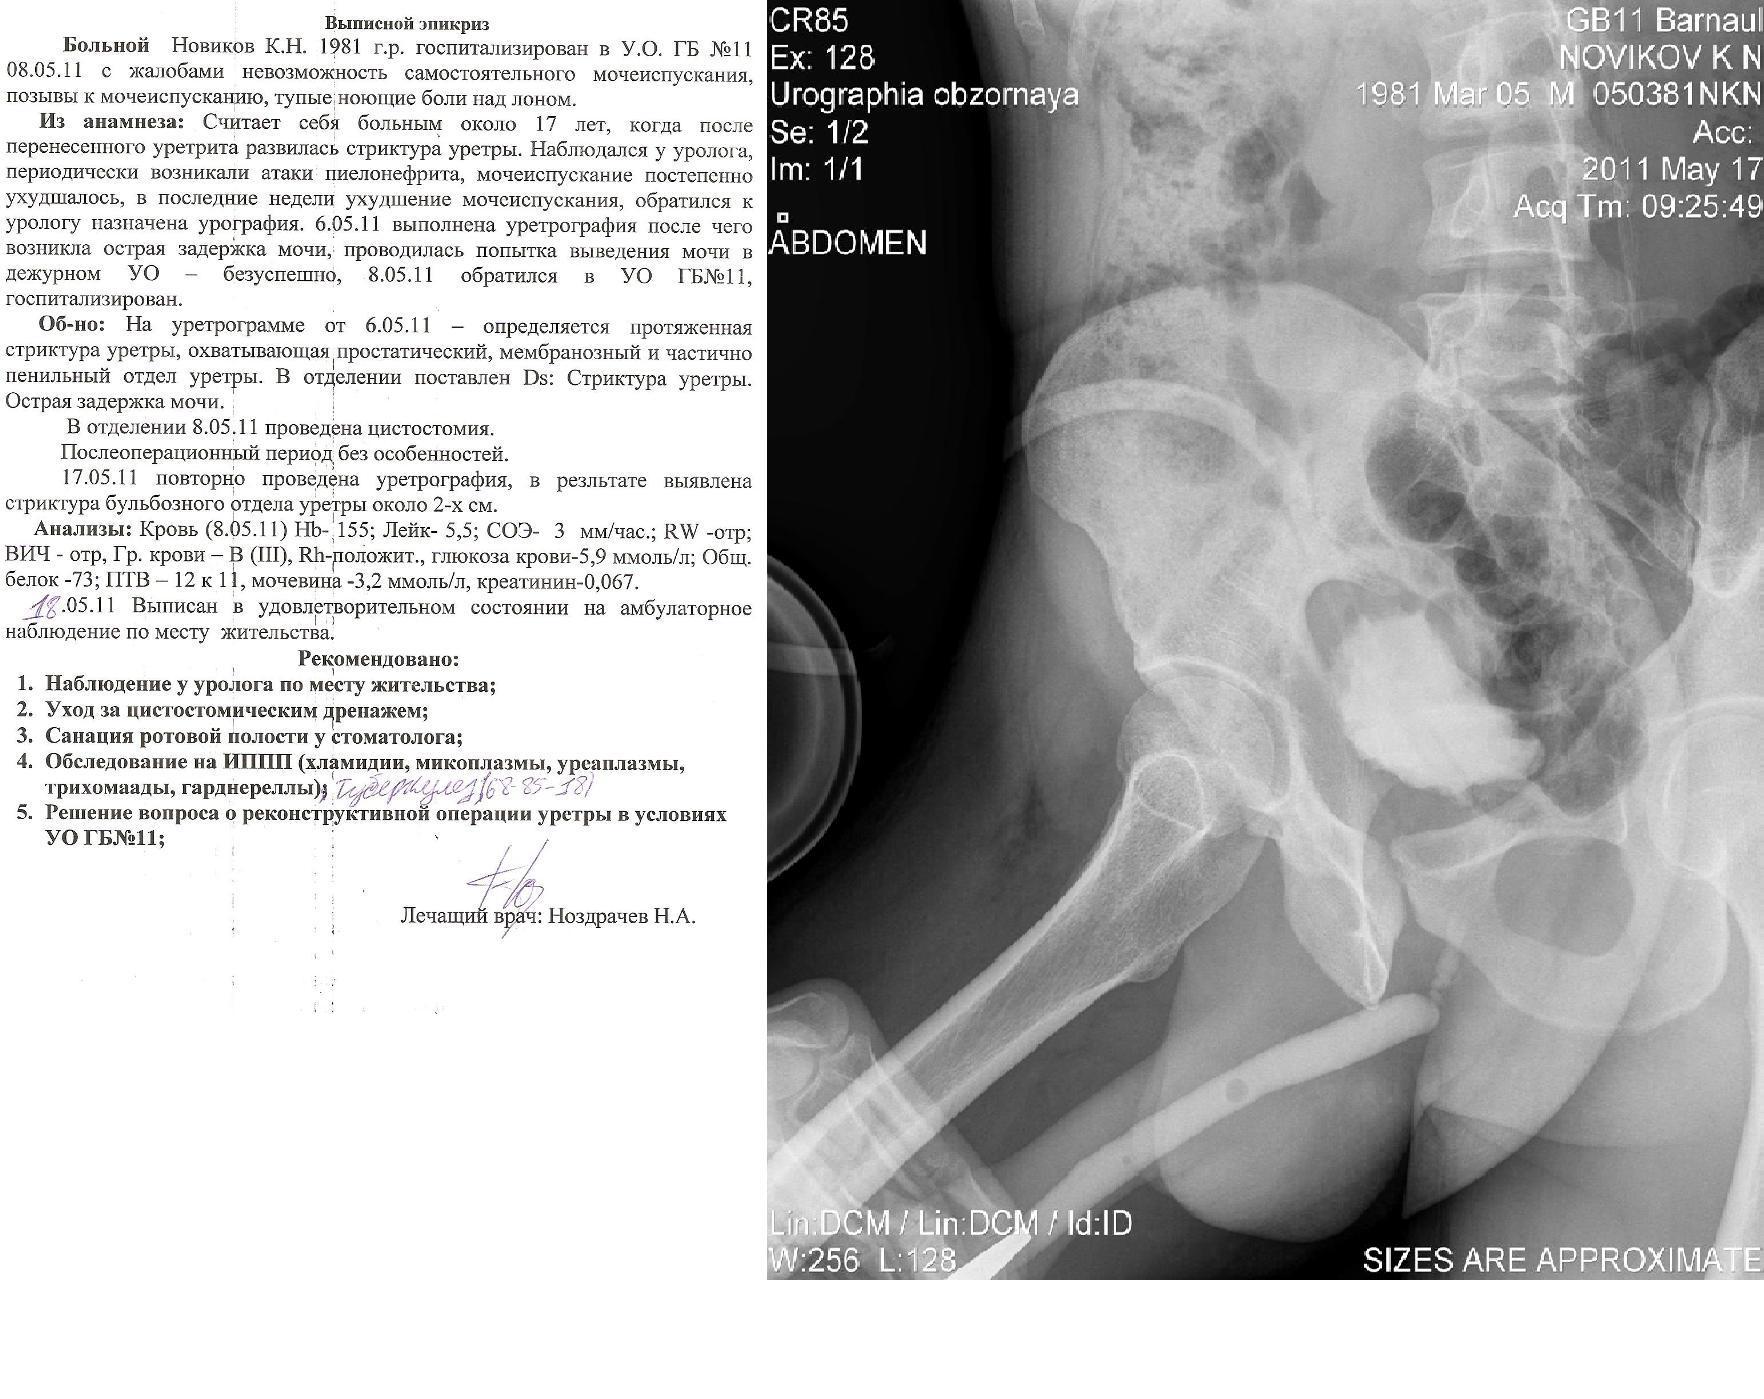

Здравствуйте! Мужу недавно сделали цистостомию, поставили диагноз: стриктура уретры (стриктура бульбозного отдела уретры около 2х см.)Стоит вопрос о "Открытой реконструктивной операции на уретре" у нас в г. Барнауле либо в Москве. Скажите пожалуйста какова вероятность успеха данной операции и как долго нужно будет находиться под наблюдением врачей, так же интересует возможно ли иное лечение при данном течении заболевания. Лечащий врач советует делать операцию в Москве, подскажите пожалуйста возможна ли бесплатная опреация, т.к. муж основной кормилец в семье, у него трое иждевенцев, я и двое детей 1 и 3 лет, наш семейный бюджет просто не потянет такую сумму. Прикрепляю фото последней уретрографии и выписку из поликлиники с точным диагнозом. Заранее большое спасибо!